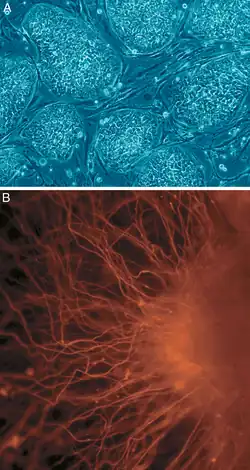

Recent research into creating miniature cortexes, known as corticopoiesis, and brain models, known as cerebral organoids, are techniques that could further the field of neural tissue regeneration. The native cortical progenitors in corticopoiesis are neural tissues that could be effectively embedded into the brain.[19] Cerebral organoids are 3D human pluripotent stem cells developed into sections of the brain cortex, showing that there is a potential to isolate and develop certain neural tissues using neural progenitors.[20]

Two models for brain tissue development are cerebral organoids and corticopoiesis. These models provide an "in vitro" model for normal brain development,[20] but they can be manipulated to represent neural defects. Therefore, the mechanisms behind healthy and malfunctioning development can be studied by researchers using these models.[20] These tissues can be made with either mouse embryonic stem cells (ESC)s or human ESCs. Mouse ESCs are cultured in a protein called Sonic Hedgehog inhibitor to promote the development of dorsal forebrain and study cortical fate.[19] This method has been shown to produce axonal layers that mimic a broad range of cortical layers.[31] Human ESC-derived tissues use pluripotent stem cells to form tissues on scaffold, forming human EBs. These human ESC-derived tissues are formed by culturing human pluripotent EBs in a spinning bioreactor.[20]